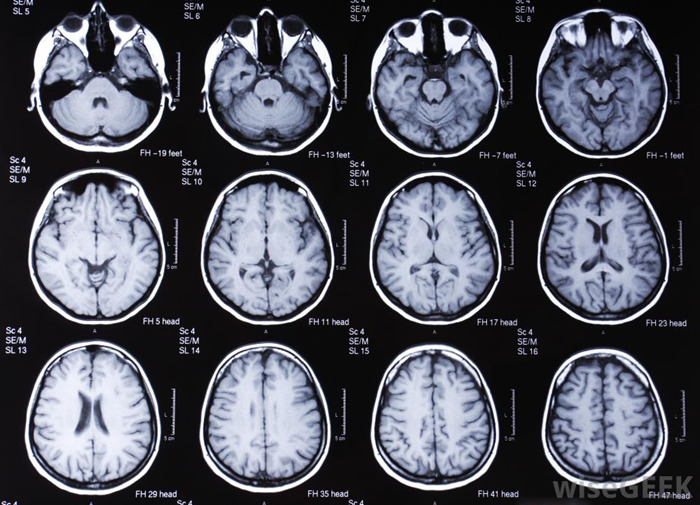

В большинстве случаев появление боли в голове при резких движениях указывает на проблемы со здоровьем. Каждая из болезней требует специфического лечебного подхода, поэтому лучше не действовать самостоятельно. Лабораторные, инструментальные и аппаратные методы диагностики помогут врачу выяснить причины состояния. По их результатам, а также с учетом индивидуальных особенностей пациента будет составлена оптимальная схема терапии.

Опухоли головного мозга

От ракового поражения органа ЦНС не застрахован никто. Нередко организм человека начинает подавать сигналы о наличии проблем на ранней стадии онкологии, но многие их игнорируют. При появлении первых же тревожных признаков необходимо отправиться к врачу.

Доброкачественные опухоли также способны провоцировать цефалгию в движении. Они давят на мозг или его оболочки, становятся причиной повышения внутричерепного давления. Подход к лечению зависит от типа новообразования, его расположения, размеров, скорости роста. Это может быть применение медикаментов, проведение химиотерапии, выполнение хирургической операции.